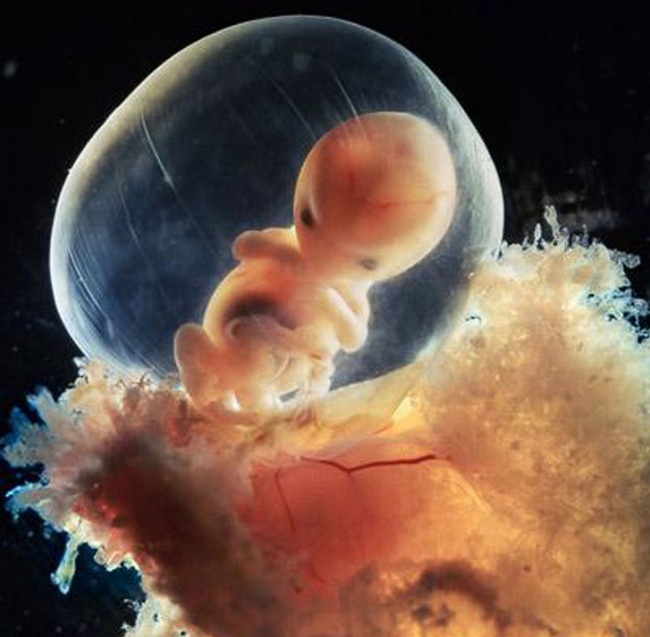

Octava semana.